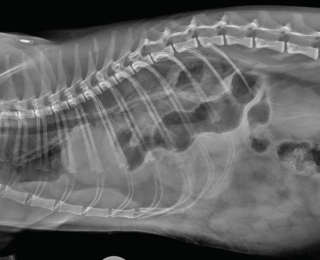

Many causes of dyspnoea are possible, and localisation is key in determining the required intervention. Thoracic trauma is common in these patients, even when there are no other visible injuries. Respiratory rate alone should not be used to exclude significant thoracic trauma and ideally survey radiographs should be performed in all patients (Figures 1 and 2) (Sigrist 2004). Table 1 gives some possible physical examination abnormalities with differentials and suggestions for diagnostics.